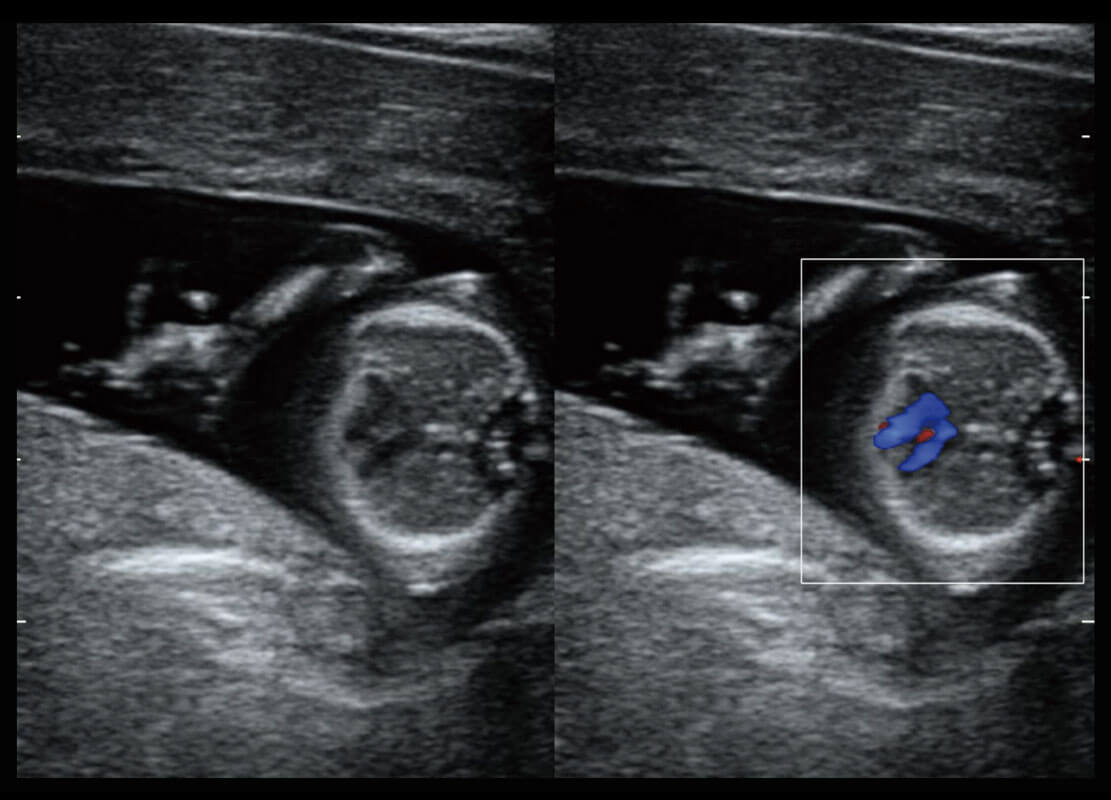

P60在胎兒早孕期超聲篩查中為您帶來(lái)優(yōu)異的圖像質(zhì)量。

早孕-胎心

P60搭載一系列胎兒心臟成像技術(shù),實(shí)現(xiàn)精細(xì)的胎兒心臟評(píng)估。

四腔切面

四腔心血流